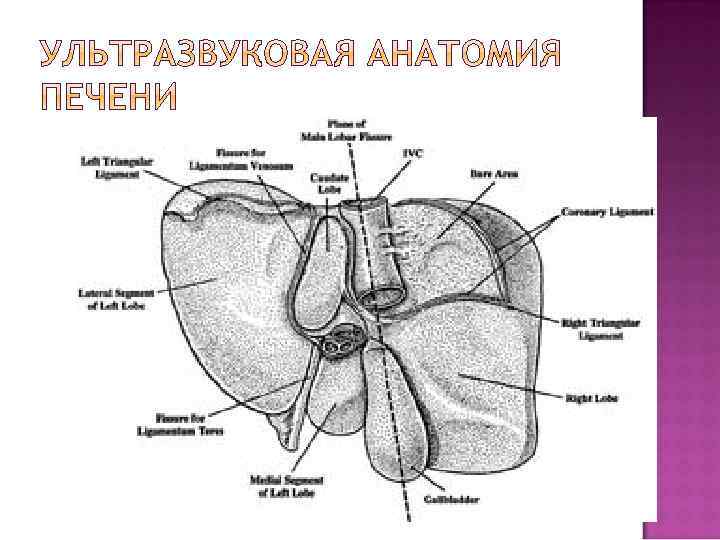

Первый сегмент соответствует хвостатой доле; отделен от 2 и 3 венозной связкой, от 4 воротами печени, от 8 - частично НПВ и устьем правой печеной вены

Второй и Третий соответствуют левой доле; отграничения от других сегментов долевые; второй занимает нижне каудальную часть изображения левой доли с центральным положением сегментарной вены леводолевой ветви воротной вены, а третий – верхне краниальную с центральным положением сегментарной вены леводолевой ветви воротной вены

1. 2. 3. 4. Анатомические ориентиры между долями: Ложе желчного пузыря – между правой и квадратной Круглая связка и борозда круглой связки – между квадратной и левой долями Ворота печени – между квадратной и хвостатой долями Выемка венозной связки (удвоенный листок капсулы и клетчатка) – между левой и хвостатой долями